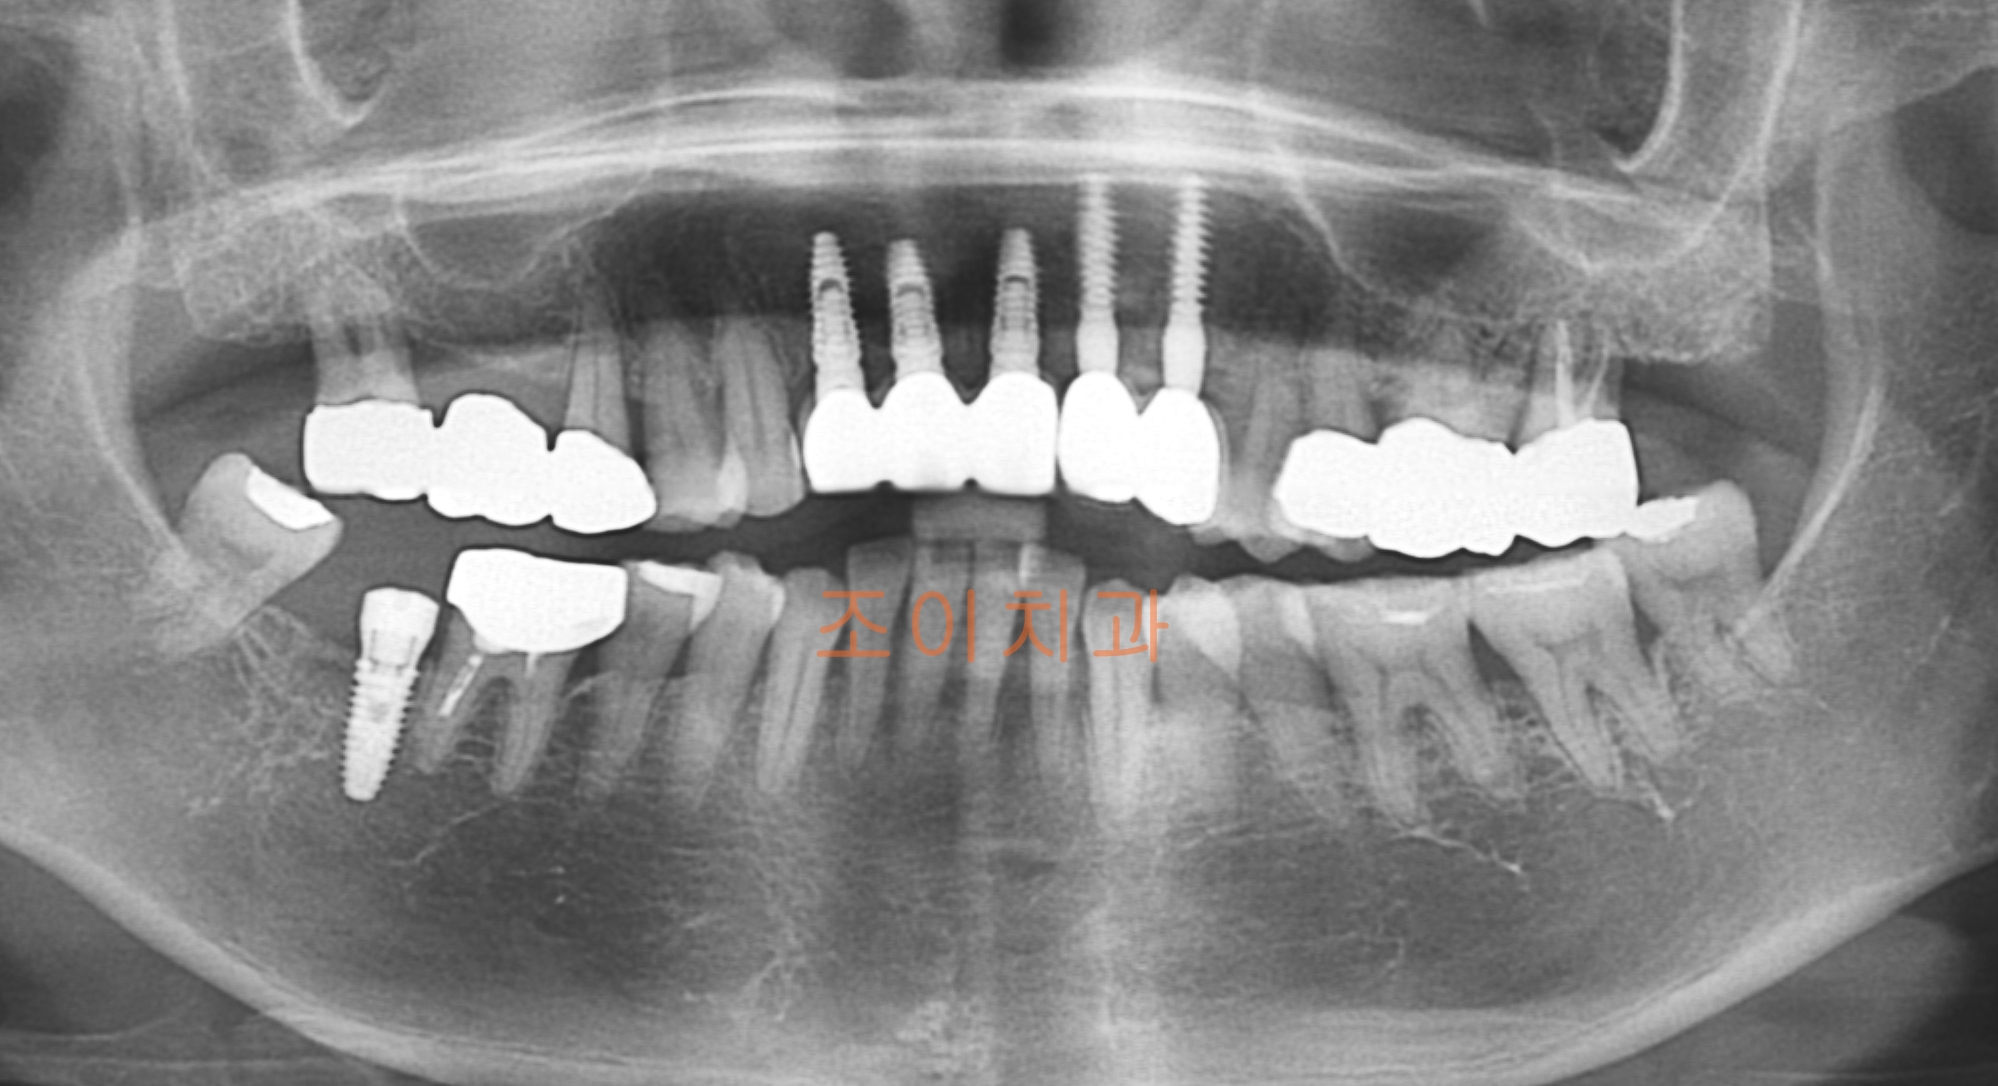

[임플란트] 제목 : 상악전치

임플란트 보철